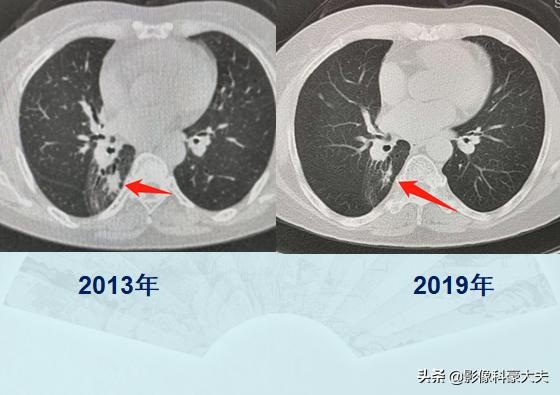

而一直以来,很多人对化疗畏之如虎,担心化疗反而会缩短寿命人财两空。其实以上手段都是对抗癌细胞的有效手段,合理使用都有机会创造奇迹:

这位60多岁的老太太,6年前查出肺癌伴肺门淋巴结转移,通过全身化疗和肺门区定位放疗,至今没有复发。这类长期带瘤生存的病例几乎每周都能遇到,晚期癌症病人的生存期也在逐步延长,未来可期!